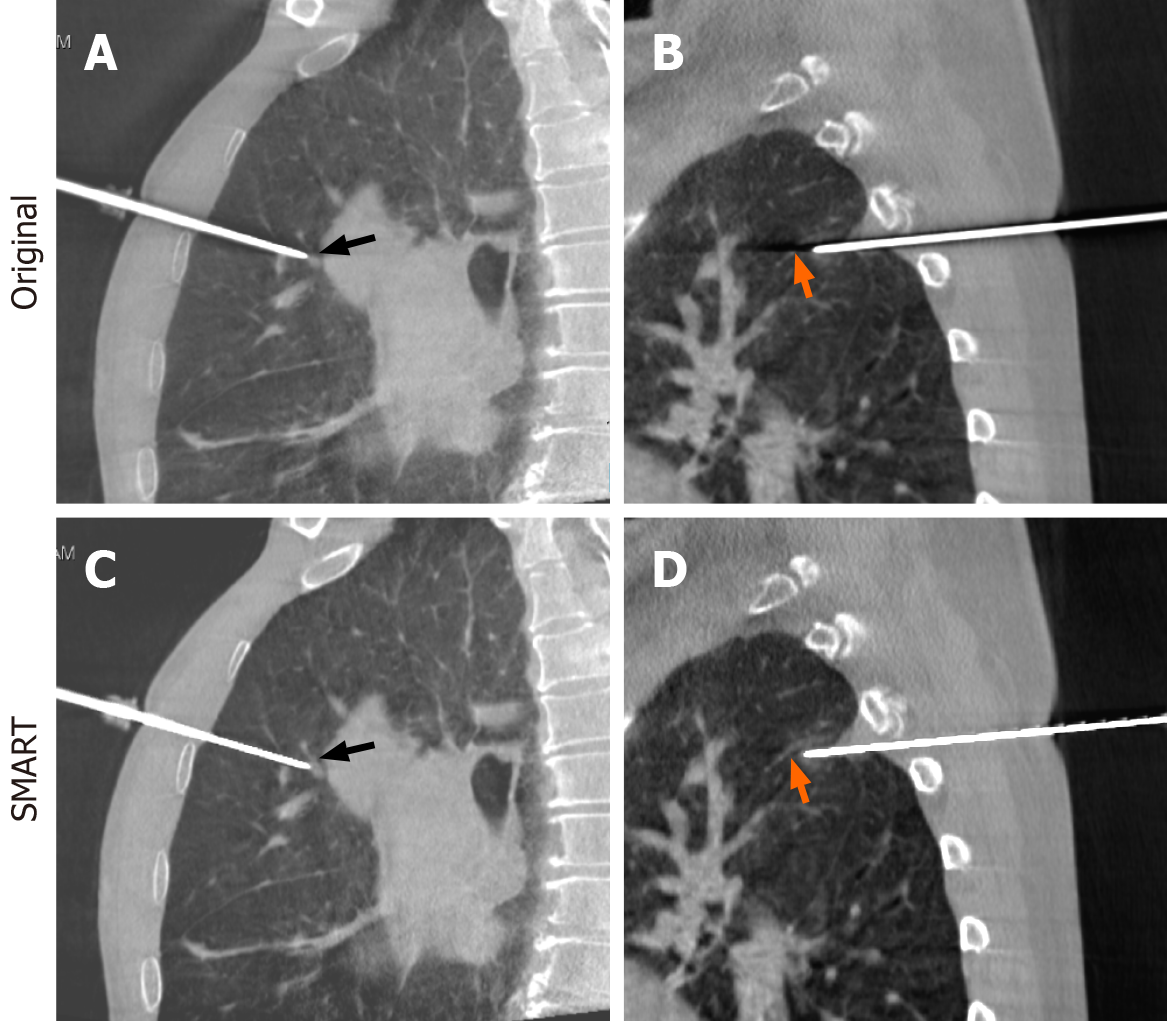

Figure 2 In the original cone-beam computed tomography images, the metal artifacts interfere with the visualization of the vessels around the target lesions.

A and B: Original cone-beam computed tomography images; C and D: After streak metal artifact reduction technique reconstruction, the vessels can be clearly visualized as indicated by the arrows. SMART: Streak metal artifact reduction technique.